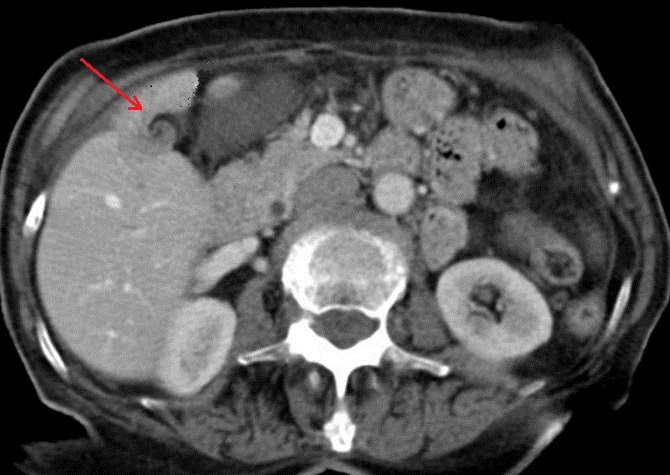

Image une calcul a

infundubulum du vesicule biliaire ( fleche

rouge ) avec epaississement de la paroi

vesiculaire : Image TDM en coupe axiale

avec contrast intraveineuse |

Meme cas en coupe coronal ( frontal ) :

Image de calcul hyperdense se en voyait tres net (

fleche rouge ) avec image de vesicule biliaire

inflamee et la dilatation de canal hepatique commun |